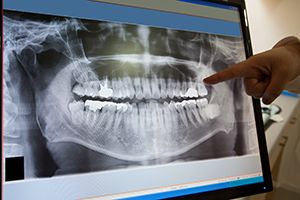

Digital X-Rays

We have introduced new digital x-rays as part of our effort to provide the safest treatment possible to our patients. Digital x-rays transmit 95% less radiation than traditional dental x-rays, and feature smaller, more comfortable sensors. Currently, our office features Digital Panorex full-face imaging. This technology allows for more accurate treatment and communication with dental specialists. The Digital Panorex can pick up unseen medical conditions and help our team make a comprehensive diagnosis.

Radiation is measured in millirems. The annual maximum occupational exposure for U.S. workers has been set at 5,000 millirems. The amount of exposures to radiation during typical medical and dental x-ray examinations are listed below:

So you would have to take 20,000 bitewing x-rays to equal the radiation in one mammogram! We would have to take almost 100,000 bitewing x-rays to reach your maximum safe yearly dose! When you weigh these facts against the serious, progressive disease processes such as cavities, gum disease, abscesses, and cancer that can go undetected without x-rays, it seems like a pretty fair, and extremely safe, trade off. There is no question that having your dental x-rays taken regularly is well worth it! We encourage you to talk to us if you have lingering questions about dental x-rays or your dental treatment.